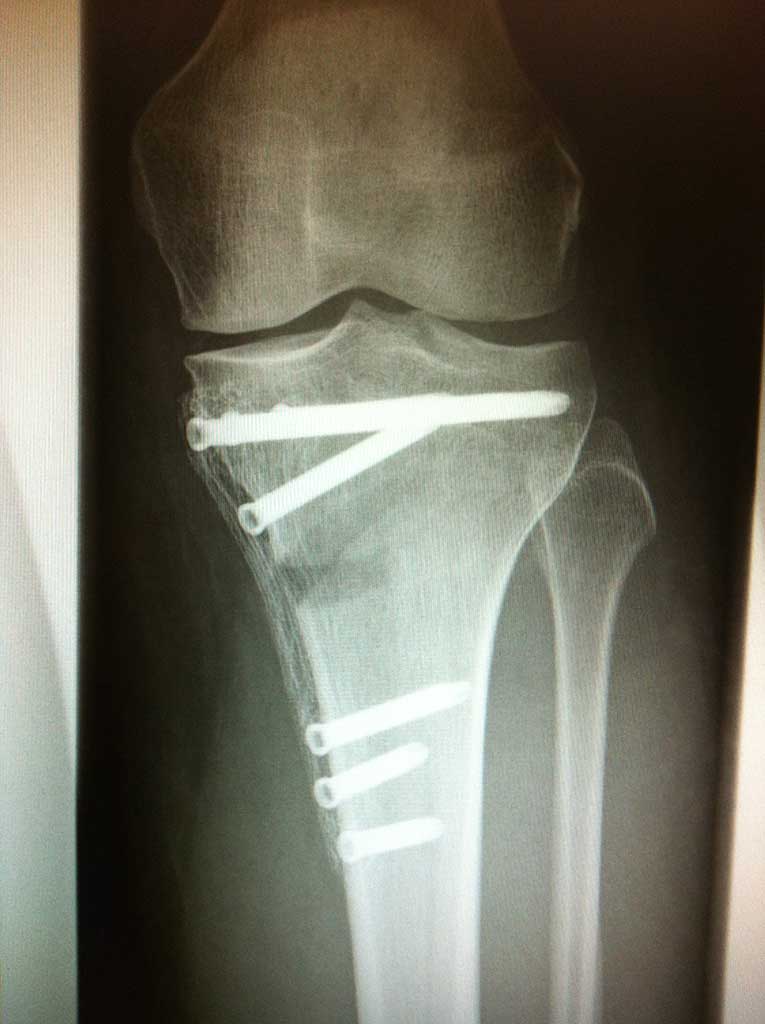

Umstellungsosteotomie Knie DonauwörthKniegelenerhalt bei Arthrose - Umstellungsosteotomie

In der Orthopädie Maximilium Donauwörth steht Ihnen ein einzigartiges Therapiekonzept zum Kniegelenkerhalt bei Arthrose zur Verfügung. Unsere langjährige Erfahrung, Expertise mit dieser Behandlung und jährliche Zahlen von durch einen Operateur durchgeführten Operationen dieser Art (250 - 300 pro Jahr) sind weltweit nur selten zu finden.

Durch dieses minimal invasives OP Verfahren, welches kniegelenksnah entweder am unteren Oberschenkelknochen oder unterhalb des Schienbeinkopfes durchgeführt wird, ändert die s.g. mechanische Beinachse und so kommt es nachhaltig zu einer bis 70% Druckentlastung des durch die Arthrose betroffenen Gelenkbereiches und somit einer wesentlichen Schmerzlinderung, wenn nicht Schmerzfreiheit.

Der Eingriff wird ausschließlich unter stationären Bedingungen entweder in Vollnarkose oder Spinalanästhesie durchgeführt. Die Operation wird durch einen zwischen 5-9cm langen Hautschnitt an dem kniegelenksnahen Knochen durchgeführt, an dem sich der mehr oder wenig ausgeprägte Beinachsenfehler befindet. Häufigerer erfolgt die Osteotomie (= Durchtrennen vom Knochen) unterhalb des Schienbeinkopfes, seltener dann am unteren Oberschenkelknochen. Dies halt allerdings keinen Einfluss auf die Scherzhaftigkeit der Operation, bzw. ihrer Nachbehandlung. Je nach Schwergrad der Arthrose wird des "O" oder "X" Bein in die Gerade umgestellt oder leicht (um wenige Grad) überkorrigiert, damit eine relevante Entlastung erreicht werden könnte.

Die neue Stellung wird mit einer kleinen, extrem stabilen Platte und Schrauben befestigt.

Die Operation dauert zwischen 40 - 70 Minuten, und in unseren Händen wird sie falls notwendig nicht selten mit einem arthroskopischen knorpelwiederherstellenden Eingriff im Knie oder Kreuzbandersatz kombiniert. Dadurch bleibt dem Patienten eine zweite Operation bzw. bis zu 3 Monaten extra Ausfall erspart!